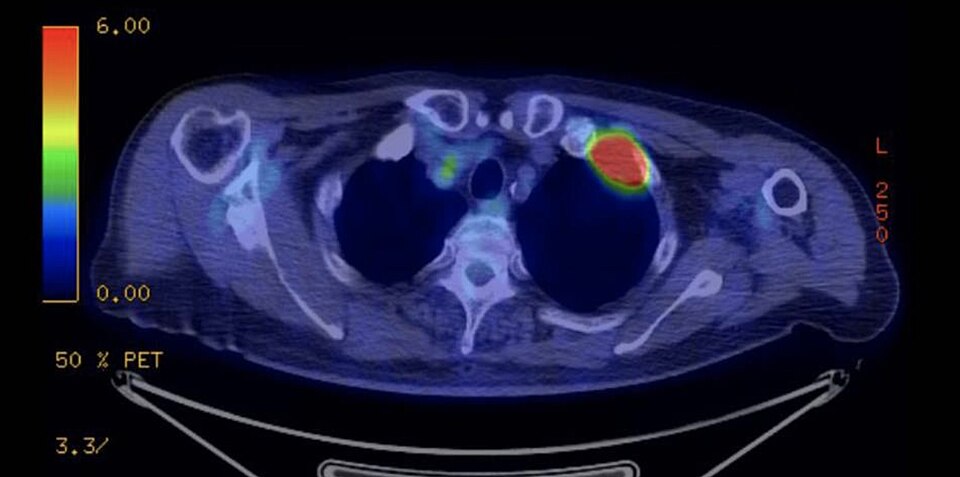

PET/CT — Pulmonary Tuberculoma

Combined PET/CT scan showing FDG-avid pulmonary tuberculoma in the chest

PET Downloaded 2026-03-15

Pet

Fdg

Wikimedia Commons: PET-CT of a tuberculoma.png